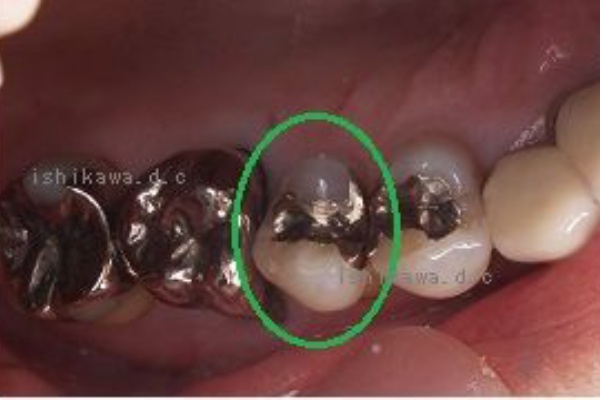

歯と歯の間の虫歯と 銀歯による歯の変色 Dr イチローのホップ ステップ ジャンプ